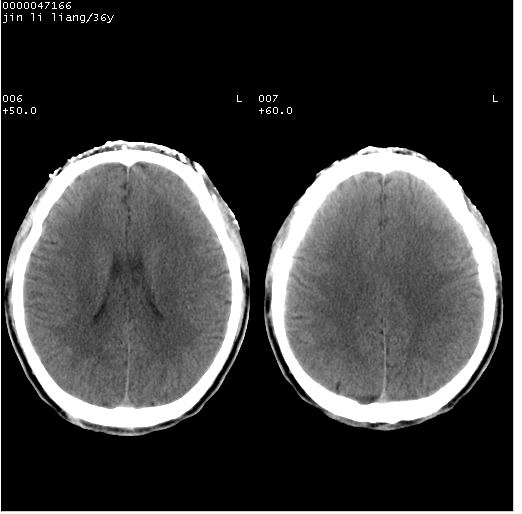

患者 男,36岁。头面部“土炮”炸伤。pe:面目全非,伤口流血不止。

临床诊断:头面部外伤。

颅脑ct轴位平扫(层厚、层距均为10mm),图像如下:

左眼球内容物浑浊其内见气体影,头面部异物.

左眼球破裂并异物,眶周、额顶部头皮及软组织挫伤并异物

迎面一炮,满脸开曝。额顶部头皮及软组织挫伤并异物,左眼球破裂积气并异物,典型的面目全非,惨不忍睹。

1左侧眼球破裂并积气,球内、框内异物。

2额部顶部软组织伤。